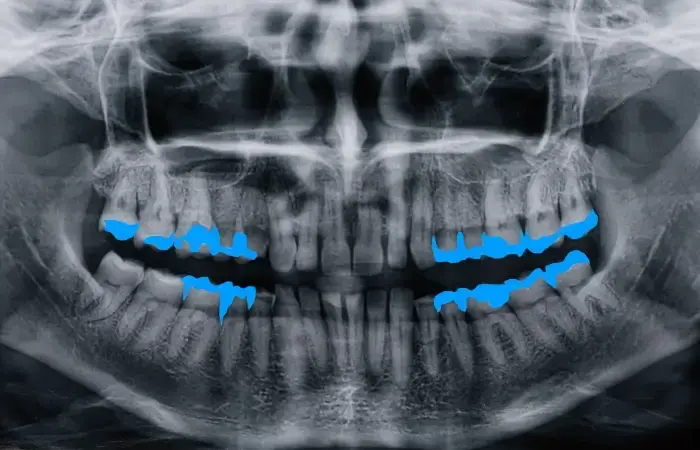

Polygons Annotation for AI in Dentistry

Utilizing the polygon annotation technique to come up with quality data for AI implementation in Orthodontistry to increase the accuracy of diagnosis and for predicting treatment outcomes.